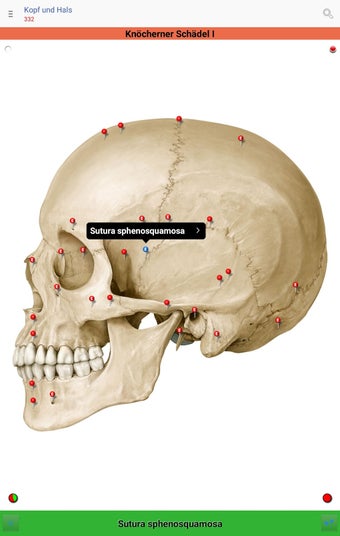

The app consists of different sections, each of which contains information about a specific part of the body. You will learn about the different organs, as well as the muscles, bones, and other important structures. You can test yourself with a unique quiz that consists of multiple-choice questions.